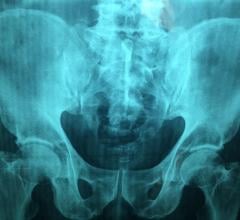

March 4, 2021 — Benign bone tumors may be present in nearly 20 percent of healthy children, based on a review of ...